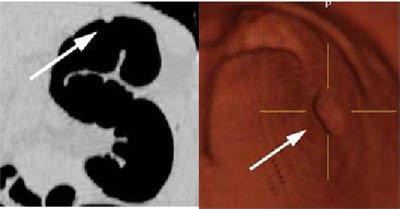

| Above, two views of a 6-mm (diameter) polyp within the splenic flexure: coronal MPR (left), and 3-D (right). Images courtesy of Dr. Riccardo Iannaccone. |

Two radiologists experienced in virtual colonoscopy read the images directly on the workstation "using a time-efficient approach, starting with 2-D, and when a suspected lesion was found, using 3-D (multiplanar reconstructions) for confirmation," Iannaccone said. The radiologists noted the size and location of all detected polyps. A single experienced gastroenterologist performed the conventional colonoscopy procedures.

According to the per-polyp results, conventional colonoscopy found 22 carcinomas, and low-dose VC detected 100% of them. Virtual colonoscopy detected 52 of 74 polyps, for an overall sensitivity of 70.3%. Virtual colonoscopy's sensitivity for the detection of polyps 10 mm and larger was 100% (13/13), 83.3% (20/24) for the detection of polyps 6-9 mm in diameter, and 51.3% (19/37) for polyps 5 mm and smaller.